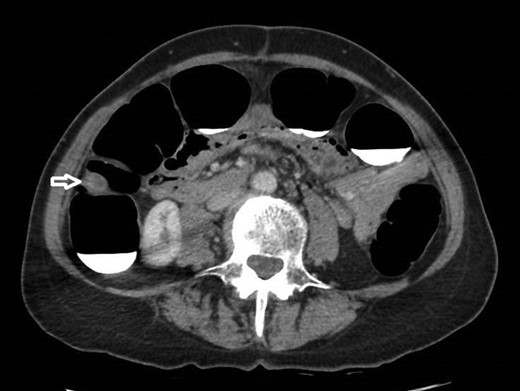

12 mm polypoidal mass (white arrow) visible on axial image of post-contrast CTVC.

In view of this CT Colonoscopy was performed, alongside a CT Chest examination. This showed a 12 mm lesion arising from the lateral wall of the ascending colon. It appeared rounded and mural-based, and displayed irregular peripheral enhancement post-contrast. It did not conform with a lipomatous lesion, with an average internal density of approximately 40 HU. No other colonic lesions were demonstrated, and no locoregional adenopathy or distant metastases were identified.